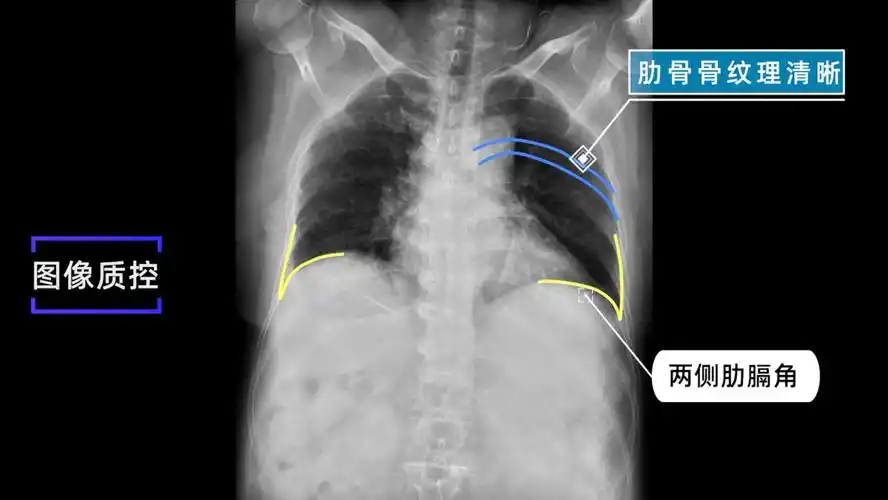

x线规范化检查膈上下肋骨摄影视频及图文详解